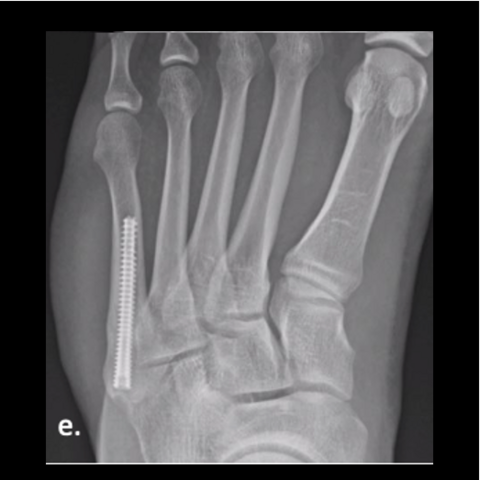

Figure 6e

Figure 6e. Plating of the fracture since screw fixation was not possible, and the patient refused external fixation for a second time.